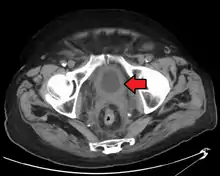

If invasive or high grade (includes carcinoma in situ) cancer is detected on TURBT, an MRI and/or CT scan of the abdomen and pelvis or urogram and CT chest should be conducted for disease staging and to look for cancer spread (metastasis).[56] Increase in alkaline phosphatase levels without evidence of liver disease should be evaluated for bone metastasis by a bone scan.[57] Although 18F-fluorodeoxyglucose (FDG)-positron emission tomography (PET)/CT has been explored as a viable method for staging, there is no consensus to support its role in routine clinical evaluations.[54]